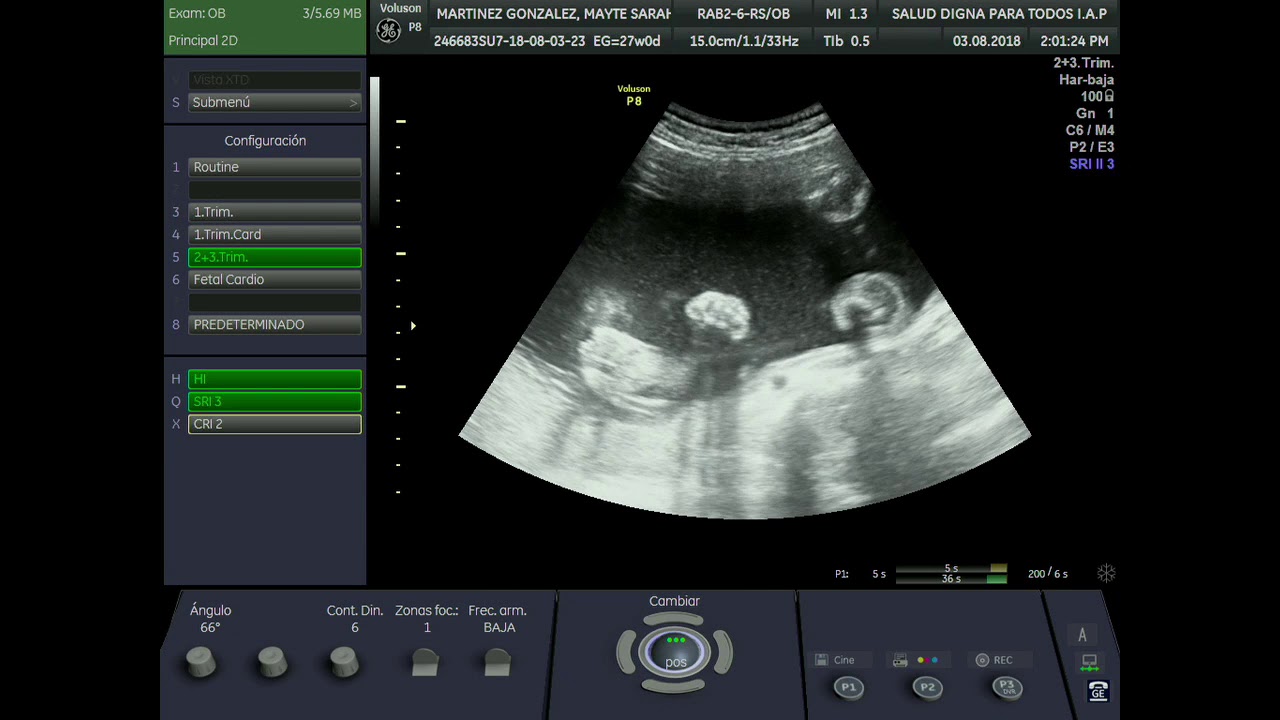

ULTRASONIDO TRANSVAGINAL PARA LA DETECCIÓN PREOPERATORIA DE

Source: sochog.cl